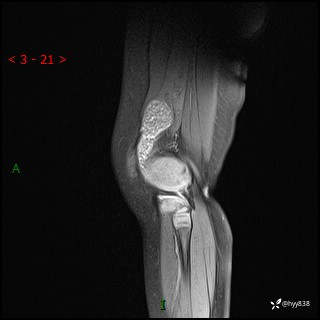

现病史:患儿1月前无明显诱因出现左下肢跛行,伴左膝关节红肿,无发热、咳嗽、恶心、呕吐等症,于当地医院就诊行X线片未提示异常,今至我院门诊就诊,门诊医师拟“跛行待查”收入院。 病后,患儿精神、食欲可,睡眠欠安,大小便通畅,体力体重无明显下降。

左膝MRI平扫